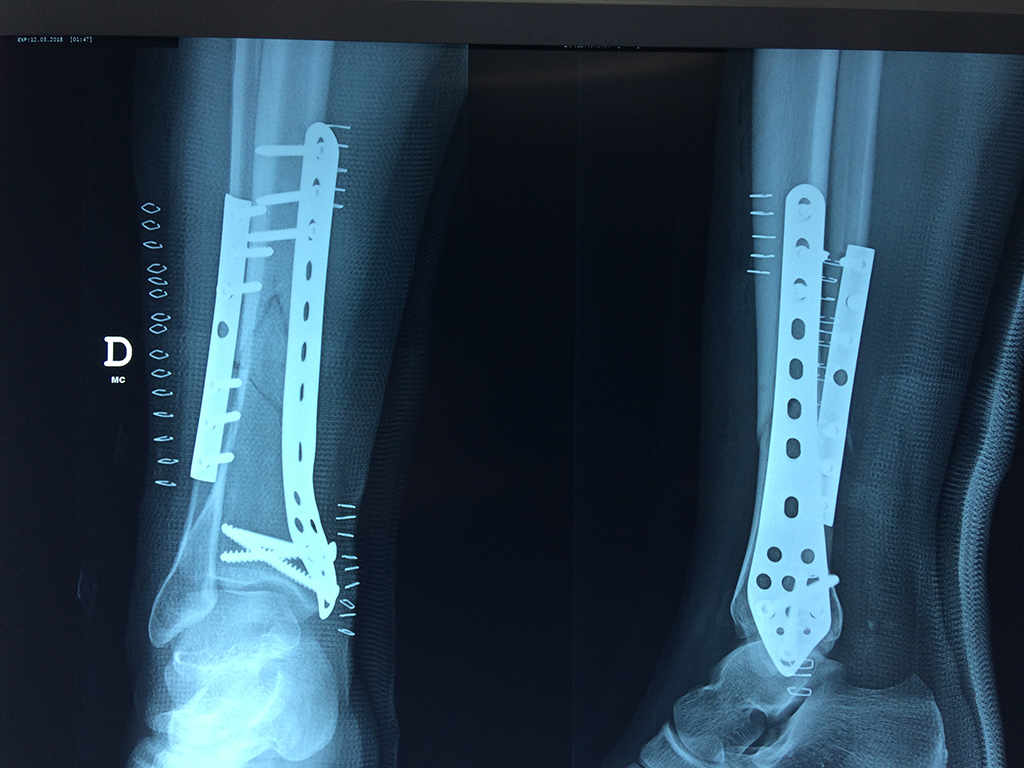

Calcaneo - Perone y Tibia

Aunque cada uno de estos huesos puede fracturarse por separado, normalmente la rotura es una lesión que se produce de forma conjunta

La mayor parte de las roturas implican a la parte proximal del hueso (parte del hueso próximo a la rodilla) o a la parte distal (parte del hueso cerca del tobillo).

Debido a la fina cobertura de piel que recubre la tibia y el peroné, las fracturas generalmente son abiertas, es decir, el hueso roto rasga la piel, atravesándola. Las fracturas de tibia y peroné generalmente se producen por un fuerte impacto o torsión.